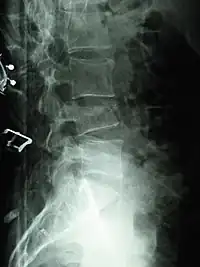

A compression fracture is a collapse of a vertebra. It may be due to trauma or due to a weakening of the vertebra (compare with burst fracture). This weakening is seen in patients with osteoporosis or osteogenesis imperfecta, lytic lesions from metastatic or primary tumors,[1] or infection.[2] In healthy patients, it is most often seen in individuals suffering extreme vertical shocks, such as ejecting from an ejection seat. Seen in lateral views in plain x-ray films, compression fractures of the spine characteristically appear as wedge deformities, with greater loss of height anteriorly than posteriorly and intact pedicles in the anteroposterior view.[3]

Compression fractures are usually diagnosed on spinal radiographs, where a wedge-shaped vertebra may be visible or there may be loss of height of the vertebra. In addition, bone density measurement may be performed to evaluate for osteoporosis. When a tumor is suspected as the underlying cause, or the fracture was caused by severe trauma, CT or MRI scans may be performed.